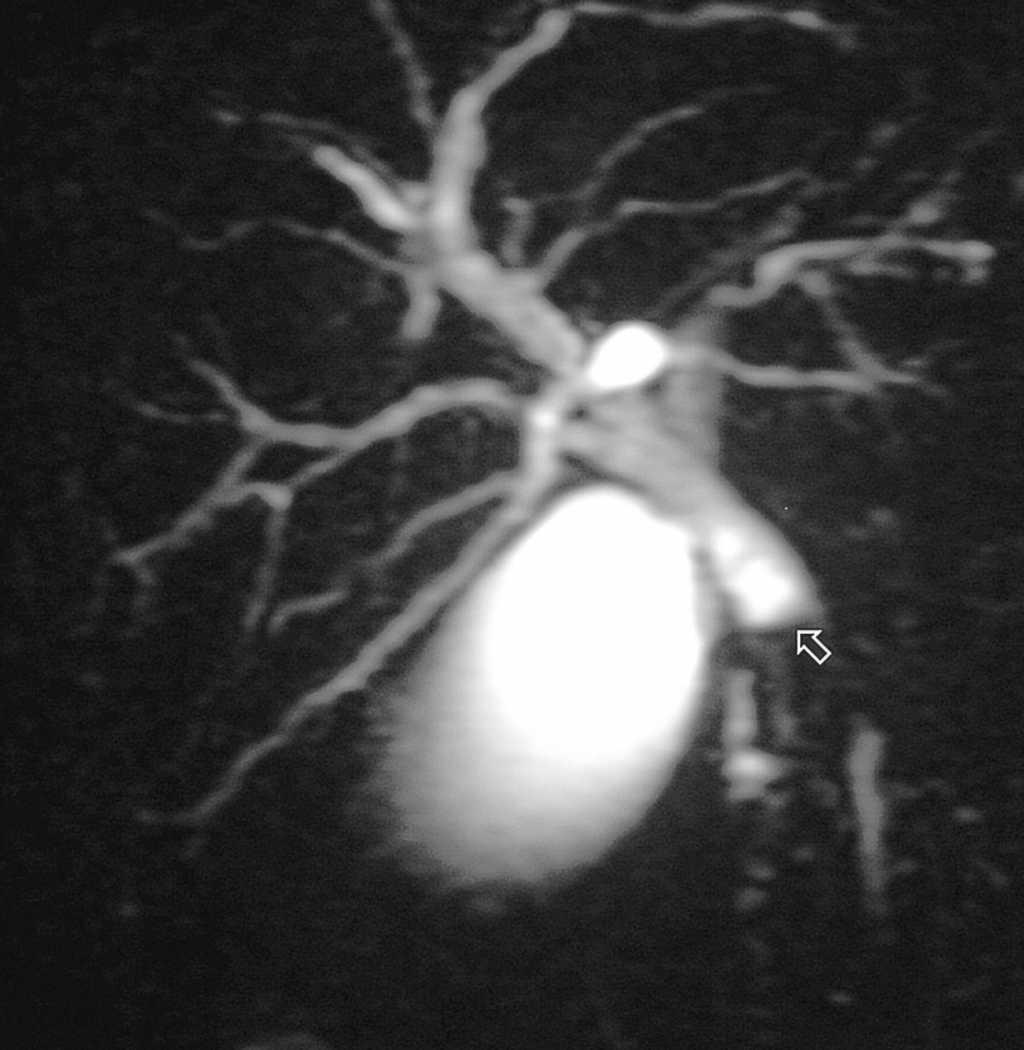

Se interviene quirúrgicamente, realizando colecistectomía y colangiografia intraoperatoria (fig. 2) que revela una imagen de stop en colédoco distal tipo "pata de cangrejo"; no se puede descartar una coledocolitiasis. Se practica una coledocotomía y se observa una tumoración sólida en el colédoco distal, por lo que se realiza una resección del colédoco distal más una extirpación de los ganglios locales y una anastomosis hepatoyeyunal con un asa desfuncionalizada en "Y" de Roux.

Fig. 2. Colangiografia intraoperatoria, con imagen en "pata de cangrejo" en el colédoco medio y dilatación preestenótica de las vías biliares.